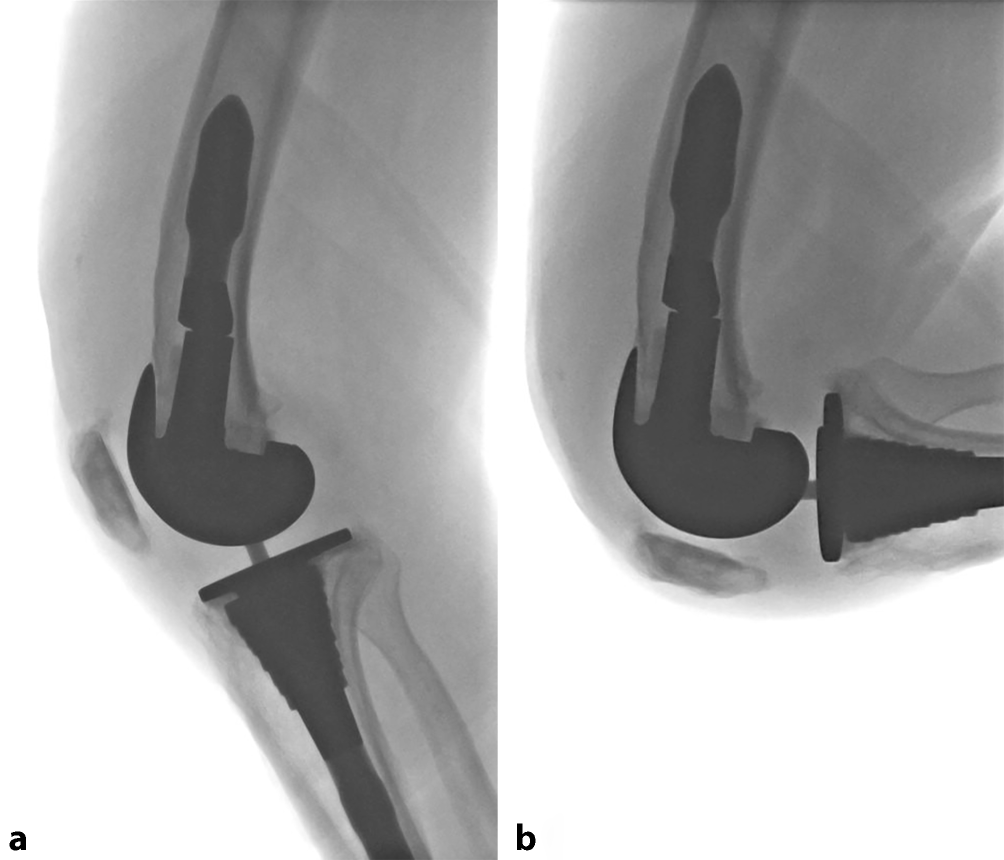

Stress-Röntgenaufnahmen, eine Aufnahme nach Kanekasu ([48]; Abb. 2) oder eine fluoroskopische Untersuchung des Kniegelenks stellen eine sinnvolle Ergänzung zur konventionellen Röntgendiagnostik dar, insbesondere bei Verdacht auf eine Instabilität. Stress-Röntgenaufnahmen werden immer beidseits und in folgenden Positionen durchgeführt: anterior-posteriorer Strahlengang mit Varus-Valgus-Stress in 15° Flexion, anterior-posteriorer Strahlengang mit Varus-Valgus-Stress in voller Extension, lateraler Strahlengang mit anterior-posteriorem Stress in 15° Flexion, lateraler Strahlengang mit anterior-posteriorem Stress in 90° Flexion (Abb. 3; [49]).

Abb. 2

Kanekasu-Aufnahme, Knie links, zur konventionell-radiologischen Beurteilung der Komponentenrotation am Femur a anterior-posterior, b seitlich